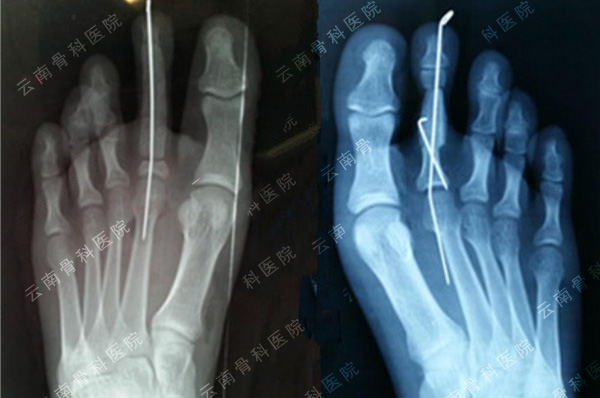

拇指Ⅴ度以上再造(7º)

示指长手指再造(1)

示指长手指再造(2)